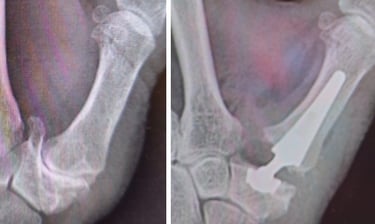

Organo muy expuesto a sufrir lesiones como las fracturas de falanges y metacarpianos, artrosis de los dedos o dedos en resorte.

Articulación muy susceptible a algunas enfermedades como la artrosis, las fracturas de radio y cubito o las lesiones de los ligamentos.

Conoce los tratamientos más avanzados para la artrosis de la mano y cómo podemos ayudarte a mejorar tu calidad de vida